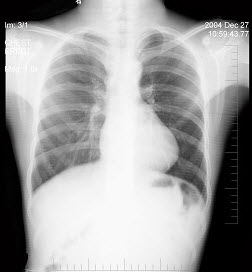

168、多项选择题

男,1岁零8个月,生长发育差,易患呼吸道感染,心悸气促,心脏正、侧位片检查如图所示,正确的描述和诊断是()

A.正位示心影向两侧扩大,心尖左移

B.肺纹理增多

C.侧位示心前间隙变窄,心后食管前三角间隙消失

D.房间隔缺损

E.室间隔缺损